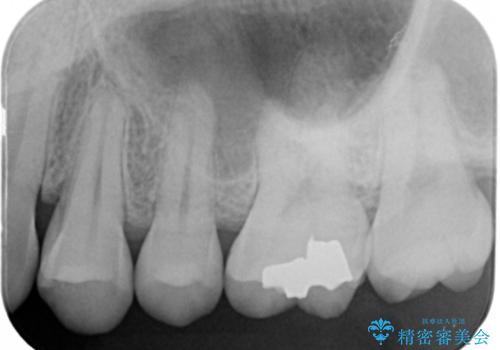

- 左上6番の銀歯のやり変えを希望し来院された患者様です。

切削量・形態を考慮し、セラミックインレーでの治療を計画しました。

銀歯直下のう蝕が深かったのでCRで裏層した上で形成、印象をしています。